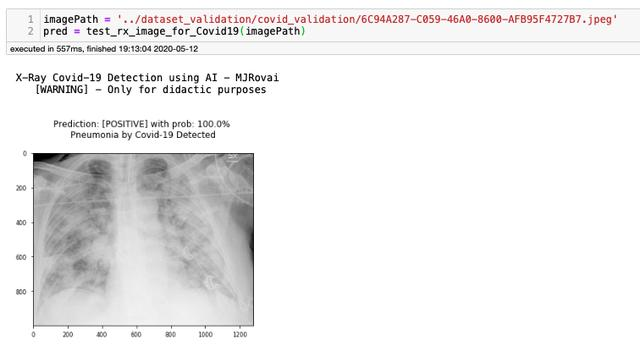

很好,我们得到了与之前相同的结果,这意味着训练的模型被正确地保存和加载。现在让我们用之前保存的8个Covid图像验证模型,为此,我们创建了另外一个函数,它是为单个图像测试开发的

def test_rx_image_for_Covid19(imagePath): img = cv2.imread(imagePath) img = cv2.cvtColor(img, cv2.COLOR_BGR2RGB) img = cv2.resize(img, (224, 224)) img = np.expand_dims(img, axis=0) img = np.array(img) / 255.0 pred = new_model.predict(img) pred_neg = round(pred[0][1]*100) pred_pos = round(pred[0][0]*100) print('\n X-Ray Covid-19 Detection using AI - MJRovai') print(' [WARNING] - Only for didactic purposes') if np.argmax(pred, axis=1)[0] == 1: plt.title('\nPrediction: [NEGATIVE] with prob: {}% \nNo Covid-19\n'.format( pred_neg), fontsize=12) else: plt.title('\nPrediction: [POSITIVE] with prob: {}% \nPneumonia by Covid-19 Detected\n'.format( pred_pos), fontsize=12) img_out = plt.imread(imagePath) plt.imshow(img_out) plt.savefig('../Image_Prediction/Image_Prediction.png') return pred_pos

在Notebook上,此函数将显示以下结果:

通过更改其余7个图像的imagePath值,我们获得以下结果:

所有图像均呈阳性,确认100%灵敏度。